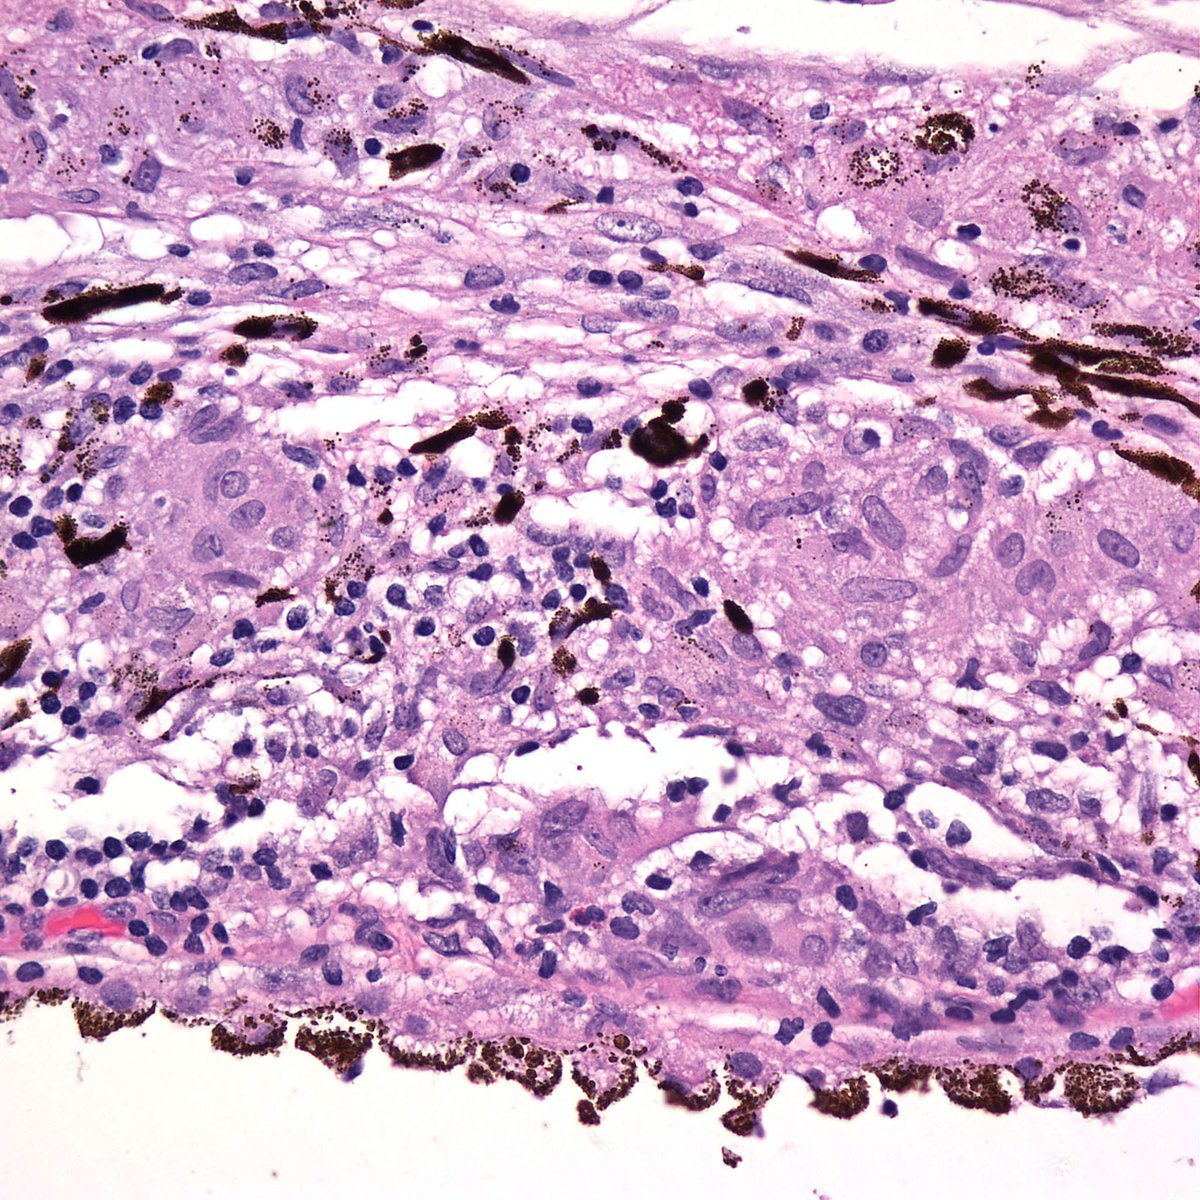

August meeting highlight: 30F w acute eye pain & redness, exposure to a farm.

Acanthamoeba keratitis!

Rare, sight threatening infection! Infection of skin & CNS too. Contact lenses

risk. Tx: topicals, surgical intervention. Great case courtesy of Drs. Cayrol & Born #Eyepath pic.twitter.com/T59rsOmdhl